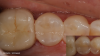

When selecting the composite shades for a case, the cervical one-third of a tooth's structure is examined to arrive at the right dentin shade. In this example, an adhesive was first placed and then cured. Next a 0.5-mm flowable layer of composite was placed and cured. Then an A3 dentin shade was placed at approximately a 1.5-mm depth and cured. Next an A2 enamel shade was placed on top. Simply two layers (three including the flowable layer), were used to create a well-blended restoration (Figure 1).

Fig 1. Two layers of a nanohybrid universal composite were used to create a well-blended restoration.

Figure 1